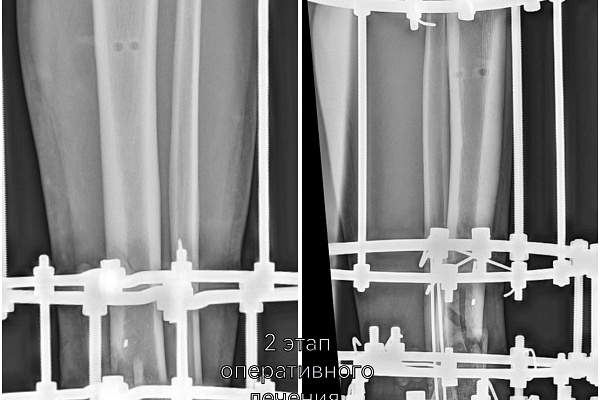

-На втором этапе первично установленный стержневой аппарат демонтирован и выполнен окончательный остеосинтез аппаратом Илизарова. На сегодняшний день это самый надежный и управляемый вариант. Данный вид фиксации позволяет проводить раннюю реабилитацию и передвигаться с нагрузкой на поврежденную ногу. Послеоперационный период проходит спокойно, мужчине назначено комплексное восстановительное лечение, включающее физиотерапевтические процедуры и занятия ЛФК, - объясняет лечащий врач Юрия, травматолог-ортопед Артём Мещеряков, выполнивший второе вмешательство.